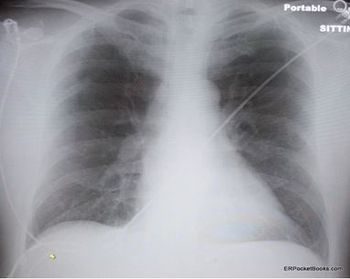

Worsening respiratory symptoms and fatigue of 6 months’ duration brought a 44-year-old woman in for evaluation. Diagnosed with asthma 2 years earlier, she was compliant with, but unresponsive to treatment. Your impressions?

The symptoms have worsened over a 2-month period. Past medical history is unremarkable. Here, review the ED chest x-ray film and ECG. Do you see any clues to a diagnosis?